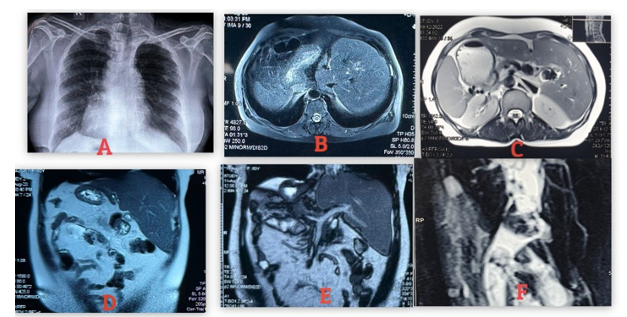

Herpes Zoster Mimmicking Renal Colic

1. Abstract 1.1. Back Ground Herpes zoster, or shingles, is a painful viral infection caused by the reactivation of the varicella-zoster virus (VZV), the same virus as chickenpox, resulting in a blistering rash, often on one side of the body or face, accompanied by burning pain, tingling, and itching.